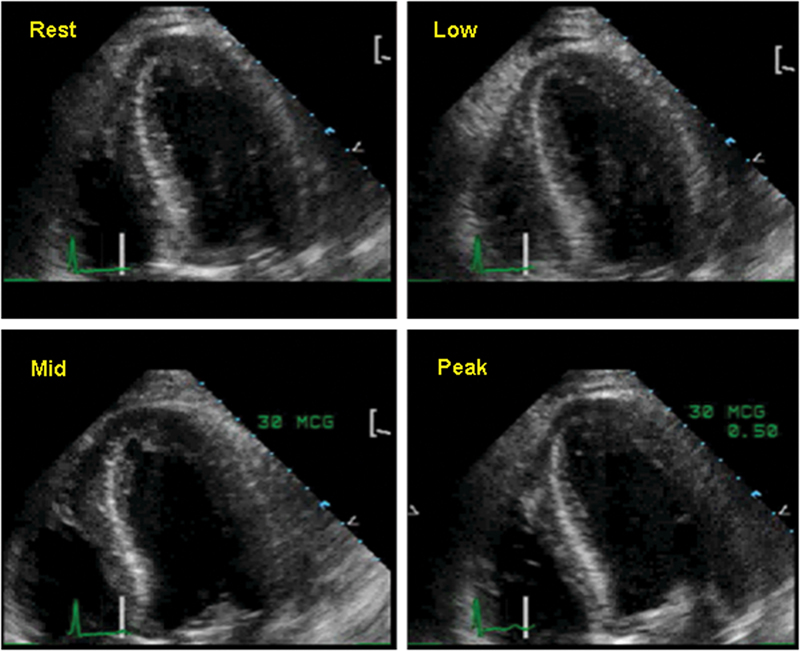

فحوصات تشخيصية لبعض امراض القلب والشرايين التاجية